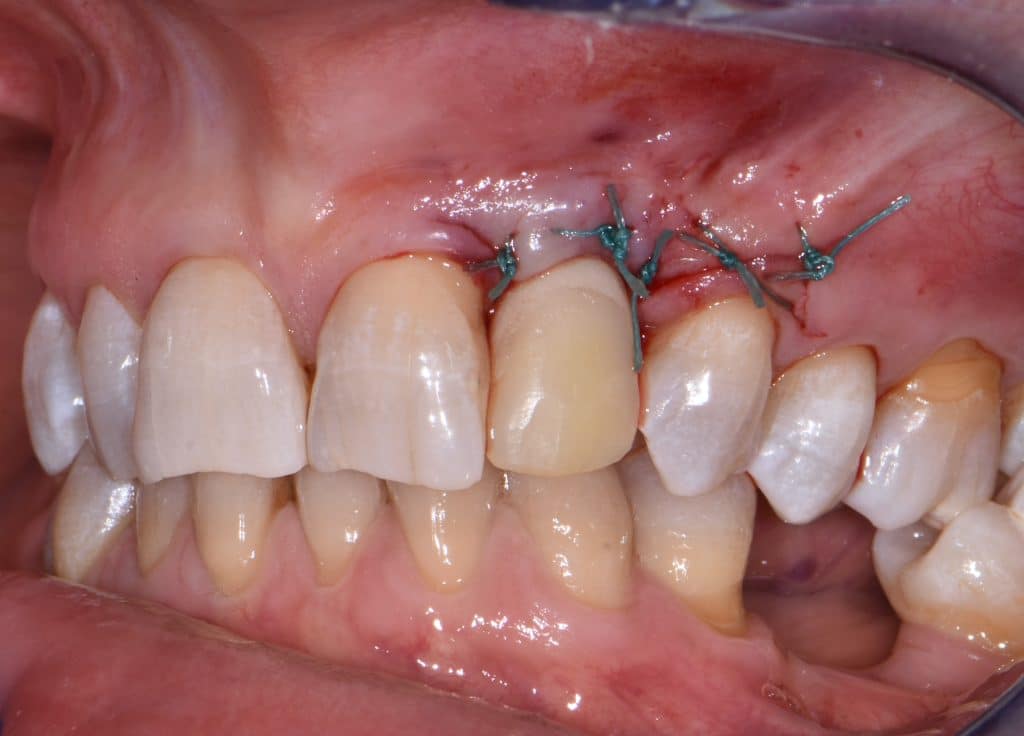

La pz N.G. di anni 52 (ASA 1) viene visitata nel mese di settembre 2017 per la mobilità ed inestetismo dell’elemento protesico 22, (foto iniziali sequenza 1) si evidenzia una frattura parziale della radice, si decide per l’estrazione ( foto sequenza 2) e sostituzione dell’elemento con un restauro implanto-protesico. Purtroppo la scarsa quota ossea apicale all’alveolo post-estrattivo (foto 2 rx) e l’alta valenza estetica dell’elemento ci rende cauti e si programma una socket preservation post estrattiva con l’ausilio delle membrane di prf (foto prf e socket sequenza 3 e 4). Durente i 5 mesi di guarigione la pz porta una protesi parziale mobile (foto 5,2) , a guarigione del sito post estrattivo si evidenzia una buona conservazione dei volumi osseo-gengivali,(foto guarigione sequenza 6) se pur presente una recessione distale all’elemnto 21.Nel mese di febbraio 2018 si procede all’inserimento di un impianto max-stability 3,75x12mm disegnando un lembo anticipato palatino per consentire un aumento dei tessuti vestibolari suturando con tecnica rool flap e trasformando l’elemento parziale mobile in una corona singola a carico immediato sul moncone temporameo applicando i concetti protesici bopt , (foto impianto moncone protesi provvisoria sequenza foto 7-8-9). Durante il periodo di maturazione dei tessuti molli vengono apportate opportune modifiche ai profili del provvisorio al fine di dare maggior spazio al tessuto gengivale, ( fotosequenza 10).Dopo circa 2 mesi dal protesizzazione provvisoria si è proceduto alla realizzazione del manufatto protesico con tecnica chair side sirona con l’ausilio del t-base (foto sequenza 11-12-13), realizzando in una sola seduta una corona in disilicato, ottenendo un risultato più che soddisfacente (Foto 14). Nel controllo a 3 mesi dal carico definitivo si apprezza la perfetta conservazione dei livelli ossei e gengivali. (foto sequenza 15).concludo con un follow up a 18 . Tengo a sottolineare che un caso come questo è stato conducibile con buoni risultati solo grazie alla piena fiducia della pz e alla sua massima motivazione e collaborazione. Ad oggi la pz sorride soddisfatta del risultato. E questo rappresenta la massima ricompensa di chi dedica tutto se stesso alla professione.